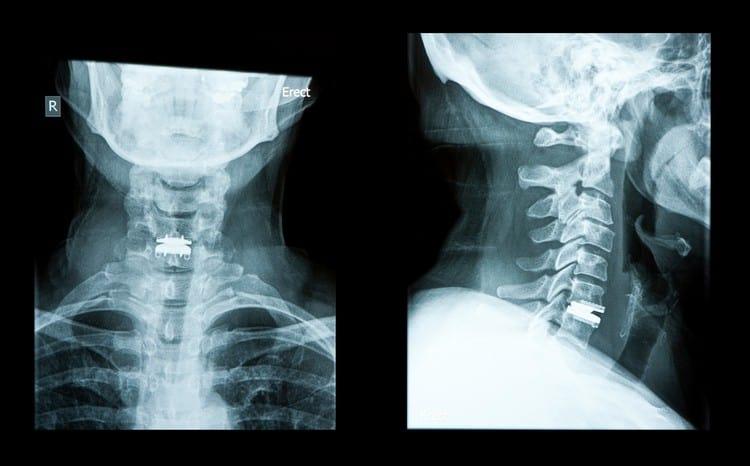

မြန်မာနိုင်ငံမှာ အရိုးအကြောခွဲစိတ်မှု ဌာနက အလုပ်များတဲ့ ဌာနပါ။ နေ့တိုင်း ကားမတိုက်တဲ့ရက်၊ ဆိုင်ကယ်မမှောက်တဲ့ရက်၊ ချော်မလဲတဲ့ရက်ရယ်မှ မရှိပဲလေ။ တစ်ခုခု ပြင်းပြင်းထန်ထန် ထိခိုက်မိလို့ အရိုးထိသွားပြီလား မသိဘူးဆို ဒီဌာနကိုပဲ ရောက်ကြလာပါတယ်။ အရိုးအကြောခွဲစိတ်မှု ဆိုတာ အရိုးအကြောခွဲစိတ်မှု ဆိုတာ အထူးပြုခွဲစိတ်မှု တစ်ခုပါ။ အရိုးနဲ့ ပတ်သက်တဲ့ ရောဂါတွေ (အရိုးအဆစ်၊ တွယ်ဆက်တစ်ရှူးတွေ ဖြစ်တဲ့ အရွတ်တွေ၊ အရွတ်တွဲတွေ) အားလုံးကို ကုသမှု ပေးပါတယ်။ သာမန်အဆစ်လွဲတာကစလို့ ကျောရိုးခွဲစိတ်မှုတွေ၊ ပေါင်ရိုးအစားထိုးမှုတွေအထိ ပါပါတယ်။ မတော်တဆ ဖြစ်တာကနေ စလို့ ရောဂါတွေအထိ ပါဝင်တာကြောင့် အရေးပေါ်ကုသမှု လိုသလို တခြားရောဂါတွေကို အေးဆေးရက်ချိန်းပြပြီးမှ ကုရတာလည်း ဖြစ်နိုင်ပါတယ်။ အရိုးအကြောခွဲစိတ်မှုက အင်မတန်ကျယ်ပြန့်ပါတယ်။ ဖြစ်တဲ့ ဝေဒနာပေါ်မူတည်ပြီး ခွဲစိတ်မှု အကြီးအသေး၊ ပြန်ကောင်းဖို့ ကြာချိန်တွေ ကွာနိုင်ပါတယ်။ အရိုးအကြောခွဲစိတ်မှုမှာ […]